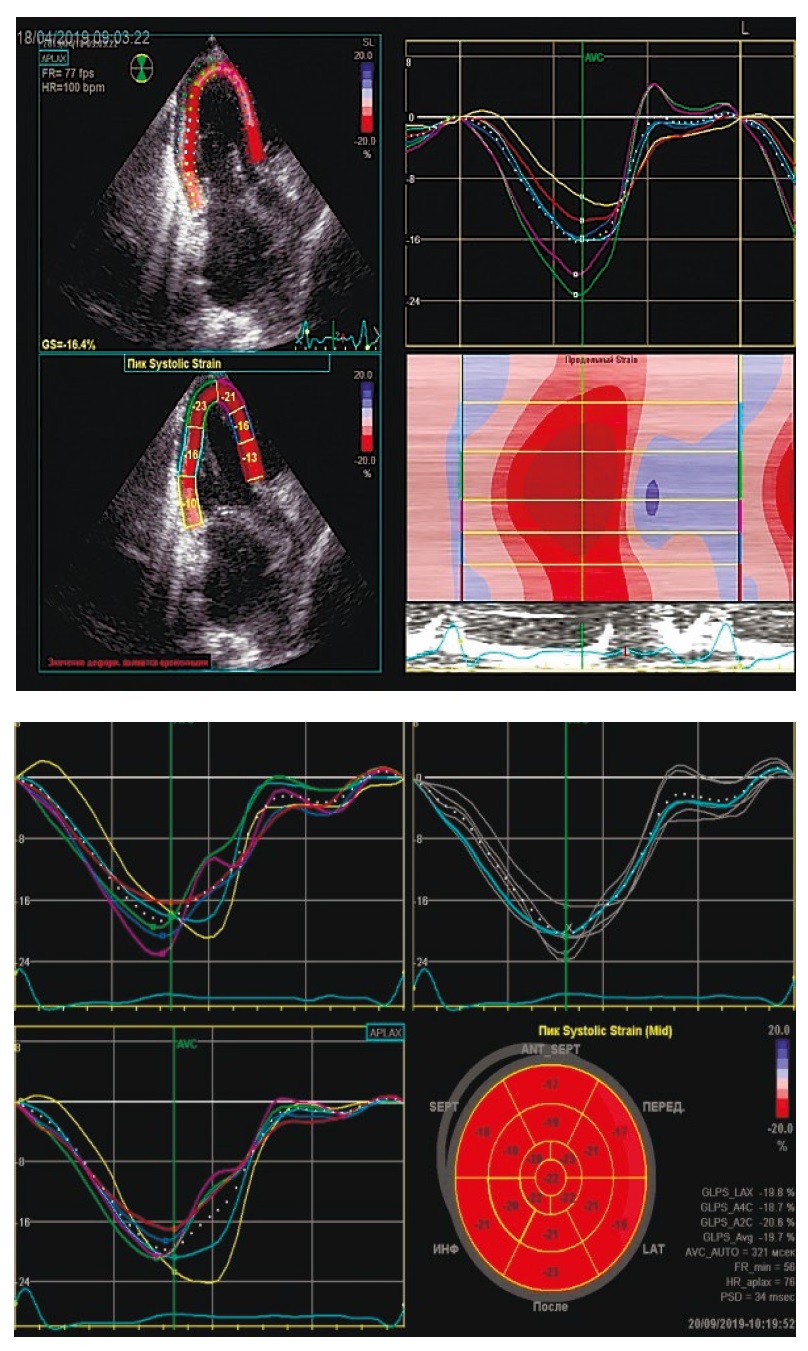

Основой разработки ЭхоКГ speckle tracking послужили данные, полученные в результате анализа динамики УЗ-изображения миокарда (серошкального) в В-модальном режиме [13]. На протяжении цикла работы сердца от кадра к кадру в 3 измерениях осуществляется мониторинг серошкальных УЗ-пятен [11, 13]. Сокращение саркомеров при сжатии левого и правого желудочка приводит к деформированию волокон миокарда, проявляющемуся в продольном и циркулярном укорочении и поперечном утолщении, что отображено на рис. 2 и 3. Значение данных процессов в случае удлинения объекта является положительным, в случае сокращения – отрицательным. Изучение циркулярной деформации проводится по короткой оси ЛЖ, продольной – из верхушечного доступа, а радиальной – из обеих позиций. При оценке систолической деформации в каждом из 17 сегментов ЛЖ она расценивается как локальная, в каждом из 3 верхушечных сечений – как средняя, а с учетом всех изученных сегментов – как глобальная [5].

Рис. 3. Speckle tracking-ЭхоКГ: определение глобальной продольной деформации.

Одним из надежных, хорошо проверенных и воспроизводимых методов измерения продольной функции ЛЖ является метод измерения глобальной продольной деформации (GLPS) с помощью speckle tracking-ЭхоКГ [15]. Эта деформация оценивается посегментарно, а также в субэндокардиальном, радиальном, эпикардиальном слое миокарда [16]. В ряде исследований показано, что GLPS является маркером раннего развития фиброза миокарда. Так, в исследовании, которое включало 86 пациентов c CН с сохраненной ФВ, показано, что GLPS уменьшался у пациентов СН в сравнении с контрольной группой без СН [17].